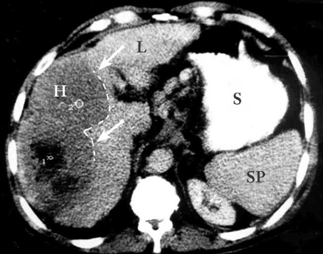

- CT המראה נגעים בכבד. בשאתות קטנות הרגישות של ה- CT ו- US זהה ולכן US משמש לסיקור באוכלוסיות בסיכון גבוה. בעזרת ה- CT ניתן לאתר גם נגעים מחוץ לכבד. ה- CT הספירלי מאפשר לנו לבצע שחזור כלי דם ולהדגים את עושר כלי הדם העוטפים את השאת. ההדגמה ב- CT היא תלת פאזית

- בדרך כלל אין צורך בביופסיה מחטית של הנגע בתנאי שניתן לראות ב- CT מאפיינים קלאסיים ל- HCC. כיוון שה- HCC היא שאת מאוד וסקולרית הרי שהיא "נצבעת" מהר וחזק בשלב ההזרקה ויש שטיפה מהירה בשלב הפורטלי המאוחר (תצלום 30.10-33.10).

| תצלום 30.10: שאת בכבד הנראית ב- CT. מימין HCC הבולטת על פני הכבד. משמאל פגם מילוי בכבד כביטוי לשאת בכבד (החץ מצביע על השאת). | |

|---|---|

| תצלום 32.10: HCC החודרת לכלי דם ויוצרת קרישים בכלי דם ורידיים. | |